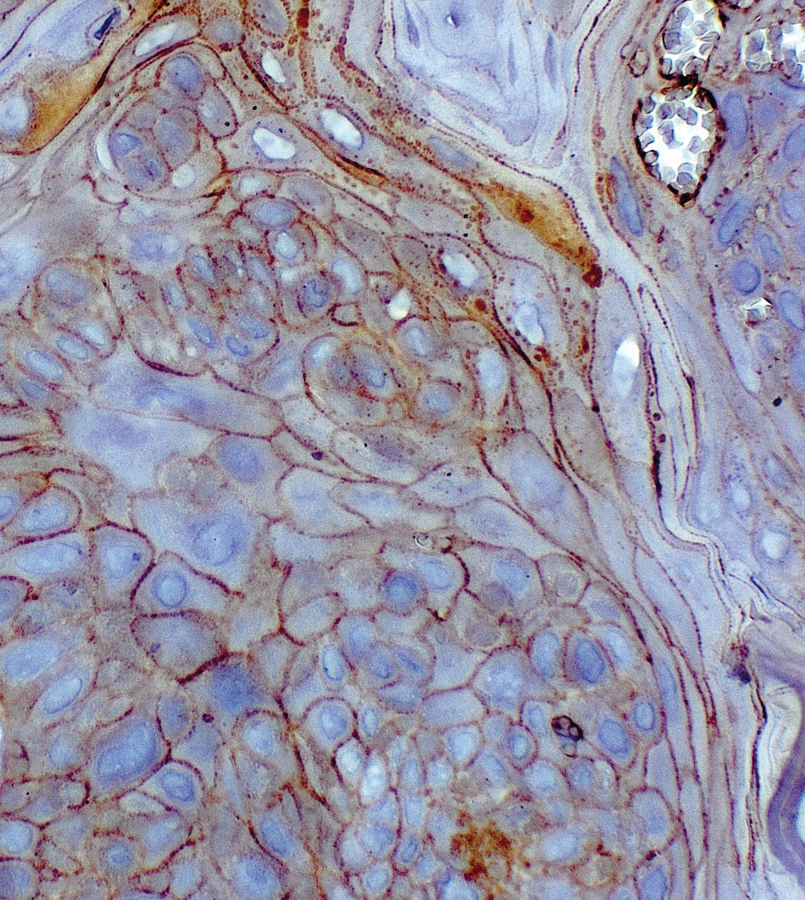

- Inmunohistoquímica de publicación nacional, como portada del Clinical Cancer Research

Inmunohistoquímica de publicación nacional, como portada del Clinical Cancer Research

El primero de enero se publicó el volumen 30 de la versión electrónica de la prestigiosa revista Clinical Cancer Research (CCR), la cual publica artículos que se centran en investigaciones clínicas y traslacionales innovadoras, que unen el laboratorio y la clínica.

En esta oportunidad, además de participar con una publicación en la que intervienen miembros de nuestro laboratorio (ver link), los editores de la revista eligieron una foto de una inmunohistoquimica de dicha publicación, como portada de la edición del 1 de enero del Clinical Cancer Research.

The cover shows a section of an oral squamous cell carcinoma lesion from a mouse challenged with 4-Nitroquinoline N-oxide, a tobacco-smoke carcinogen surrogate, and treated with C59, a Porcupine inhibitor. Immunohistochemical staining shows reduced non-phosphorylated (active) β-catenin expression at tumor cell borders. For details, see the article by Peña-Oyarzún and colleagues on page 209 of this issue